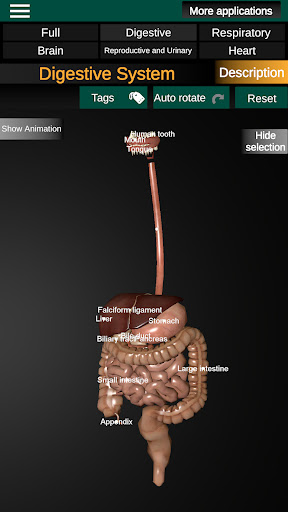

Internal Organs in 3D Anatomy لـ Vodafone Smart N9 Lite

(الأجهزة الداخلية في)

Internal Organs 3D Anatomy 3.4

يمكنك هنا تنزيل ملف حزمة تطبيق أندرويد "Internal Organs 3D Anatomy" الخاصة بجهازVodafone Smart N9 Lite مجانًا، نسخة ملف حزمة تطبيق أندرويد - 3.4 للتحميل على Vodafone Smart N9 Lite اضغط ببساطة على هذا الزر. إنه سهل وآمن. نحن نقدم فقط ملفات حزمة تطبيق أندرويد الأصلية. إذا انتهكت أية مواد موجودة في الموقع حقوقك قم بإبلاغنا من خلال